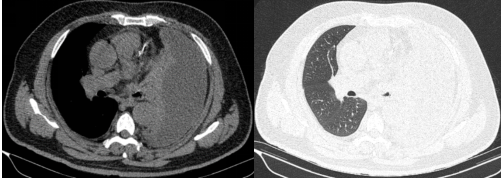

入院时CT显示:左侧胸腔被积液填满,如同一个巨大的"脓袋"压迫着正常肺组织。

棘手的是,传统穿刺引流如同"抽丝剥茧",抽出近2000ml腥臭脓液后,复查CT仍见残留大量纤维分隔包裹,配合强力抗生素治疗,患者仍然持续高烧不退。

历经4小时鏖战,手术团队成功拆除"定时炸弹"。术后第二天,患者体温即开始逐渐下降,后续继续全身应用抗生素、胸腔灌注药物、控制血糖、营养支持等综合治疗,患者病情迅速好转,复查肺CT恢复良好,患者对治疗效果表示满意。